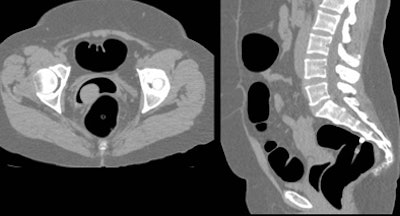

![]() |

| Occasional errors occurred with the use of unsupervised technologists to perform virtual colonoscopy scans. In one instance, a substitute technologist who had not been trained in virtual colonoscopy performed a vaginal intubation and insufflation in error. After the tube was removed and reinserted in the rectum, the colon was insufflated successfully and the patient scanned without incident. Image courtesy of Dr. Arnold Friedman. |